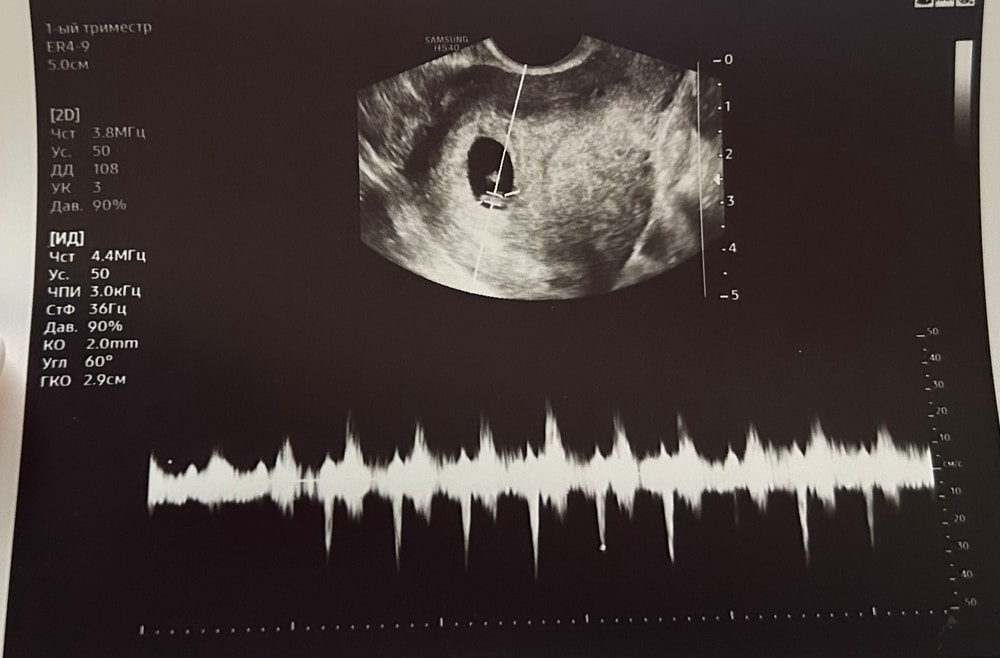

Можно ли по узи посчитать чсс?)

ИИ тоже странную формулу предлагает, неправильный результат получается

ЧСС = (36 Гц × 60) / 2 = (2160) /2 = 1080 ударов в минуту.

Мне ии пишет что дд 108 это и есть чсс

Kristen , наверно, ты права)) его подсчеты похожи, только ноль убрать, видимо, неправильно считал